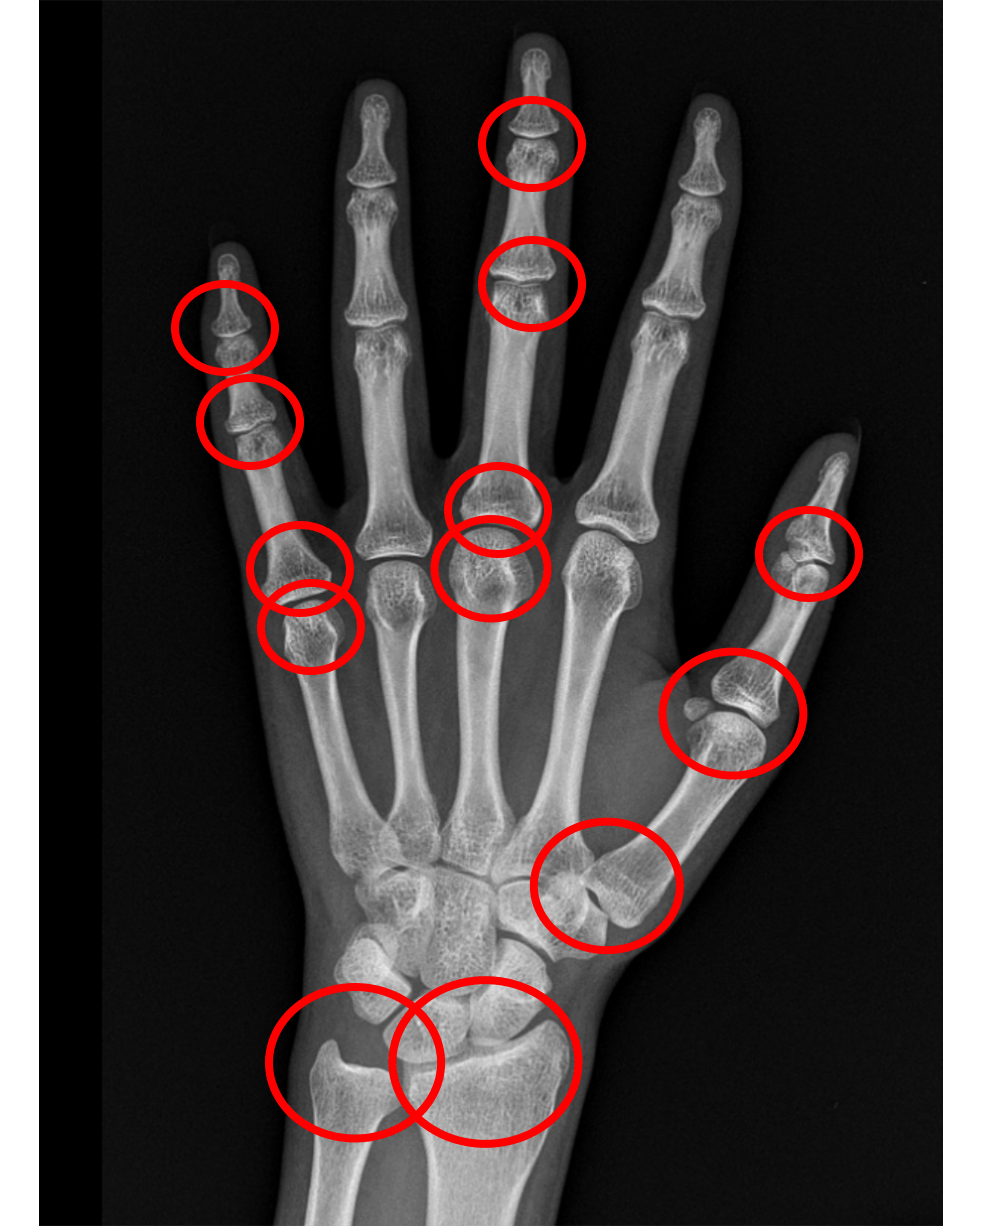

用中华05计分法看骨龄避免误差

鉴定分析:中华05标准鉴定数据为14.2岁骨龄.